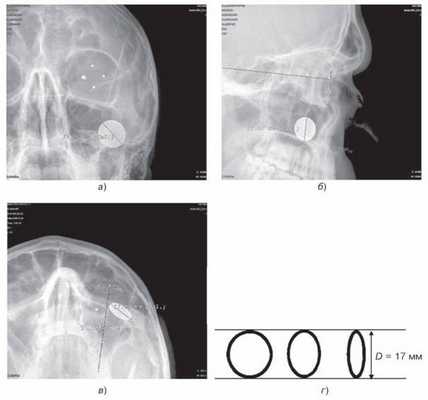

Рентгенограмма в прямой плоскости. Центрация луча производится «на зрачок», т. е. линии светового центратора, при условном продолжении их с темени на орбиту, должны пересекаться на зрачке, а центральный луч — совпадать с осью глаза. На снимке видна слабая кольцевидная тень протеза и четыре точечные метки. Показателем качества снимка служит почти концентричное положение тени протеза в контуре глазницы. Допускается смещение меток вокруг оси без отклонения глаза (рис. 77, а).

Боковой снимок выполняется в положении лежа на спине боковым лучом с центрацией на наружный угол глаза. На снимке видна трапециевидная тень протеза. Критерий качества снимка — расположение меток протеза на одной линии (см. гл. 13, рис. 125, а). Максимально допустимое расхождение меток на

3- 9 часов — 2 мм (рис. 77, б).

Аксиальный снимок (подбородочная укладка). Взгляд фиксируется прямо вперед параллельно столу. На снимке видна тень протеза со свинцовыми метками (см. гл. 13, рис. 125, б). Об удовлетворительном качестве снимка свидетельствует расположение меток на одной линии. Максимально допустимое расхождение меток, обозначающих 6 и 12 часов, — 2 мм.

Фокусное расстояние для всех трех снимков равно 60 см.

Рис. 76. Схема прицельных рентгенограмм левой орбиты с индикацией глазного яблока протезом Комберга—Балтина: а — прямой; б — боковой; в — аксиальный: (7) — проекция горизонтальной плоскости черепа, (2) — проекция горизонтальной плоскости орбиты, (3) — проекция вертикальной плоскости орбиты; (4) — проекция плоскости лимба, (5) — проекция сагиттальной оси; г — протез Комберга—Балтина; д — схемы-измерители. Пояснения в тексте.

Индикация глазного яблока и анализ полученной информации производятся классическим методом (рис. 77).

Рис. 77. Цифровые рентгенограммы левой глазницы в трех (а — прямая, б — боковая, в — аксиальная) проекциях, с индикацией глазного яблока протезом Комберга—Балтина. Для калибровки на кожу вблизи орбиты прикреплен рент- генконтрастный диск (монета 10 копеек); г — варианты формы рентгеновского изображения диска в зависимости от ракурса. Пояснения в тексте.